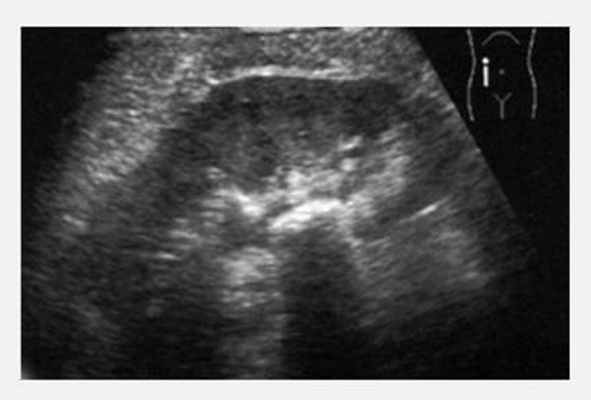

Мочекаменная болезнь, конкремент в лоханке почки.

Конкремент в устье мочеточника